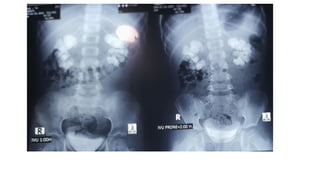

X-Ray of

encrusted

stent

encrusted stent